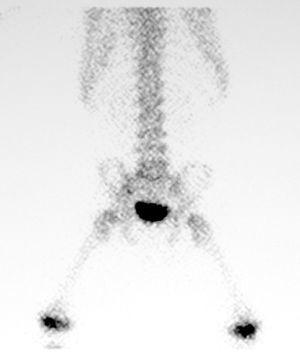

El hemograma, los tiempos de coagulación y la proteína C reactiva fueron normales. La velocidad de sedimentación globular (VSG) de 42 mm/h, indicaba un probable proceso inflamatorio. En la radiografía de columna vertebral se observó una mala definición de los platillos vertebrales inferior de L5 y superior de S1, con aparente esclerosis (fig. 1). La gammagrafía con 99mTc mostró un aumento de captación leve, de morfología lineal, en área teórica de las carillas articulares de cuerpos vertebrales L5-S1 (fig. 2).

Figura 2. Gammagrafía con 99mTc, aumento de captación de morfología lineal en área teórica de las carillas articulares de cuerpos vertebrales L5-S1.

La radiografía simple puede mostrar alteraciones en los cuerpos vertebrales o en el disco, que se encuentra más adelgazado a partir de la segunda semana. La gammagrafía ósea, que pone de manifiesto un aumento de la captación del trazador en el área afectada, ha demostrado ser un método seguro de diagnóstico de infección del espacio discal pero no permite diferenciar entre discitis y otras causas de dolor de espalda. La tomografía computarizada (TC), que revela áreas de hipodensidad y destrucción trabecular, cortical y de los platillos, no añade valor en el manejo de la discitis ya que meramente provee una información extra de una lesión que ya ha sido revelada por las radiografías. Desde que la RM está disponible, la TC no es requerida. La RM permite el diagnóstico temprano cuando los signos clínicos son difíciles de interpretar y la visualización de posibles complicaciones locales que podrían requerir una intervención quirúrgica, como protrusión severa del disco vertebral con atrapamiento de la raíz del nervio espinal o un absceso grande paraespinal7. Los beneficios de la RM compensan los bajos riesgos de la sedación en este grupo de edad.